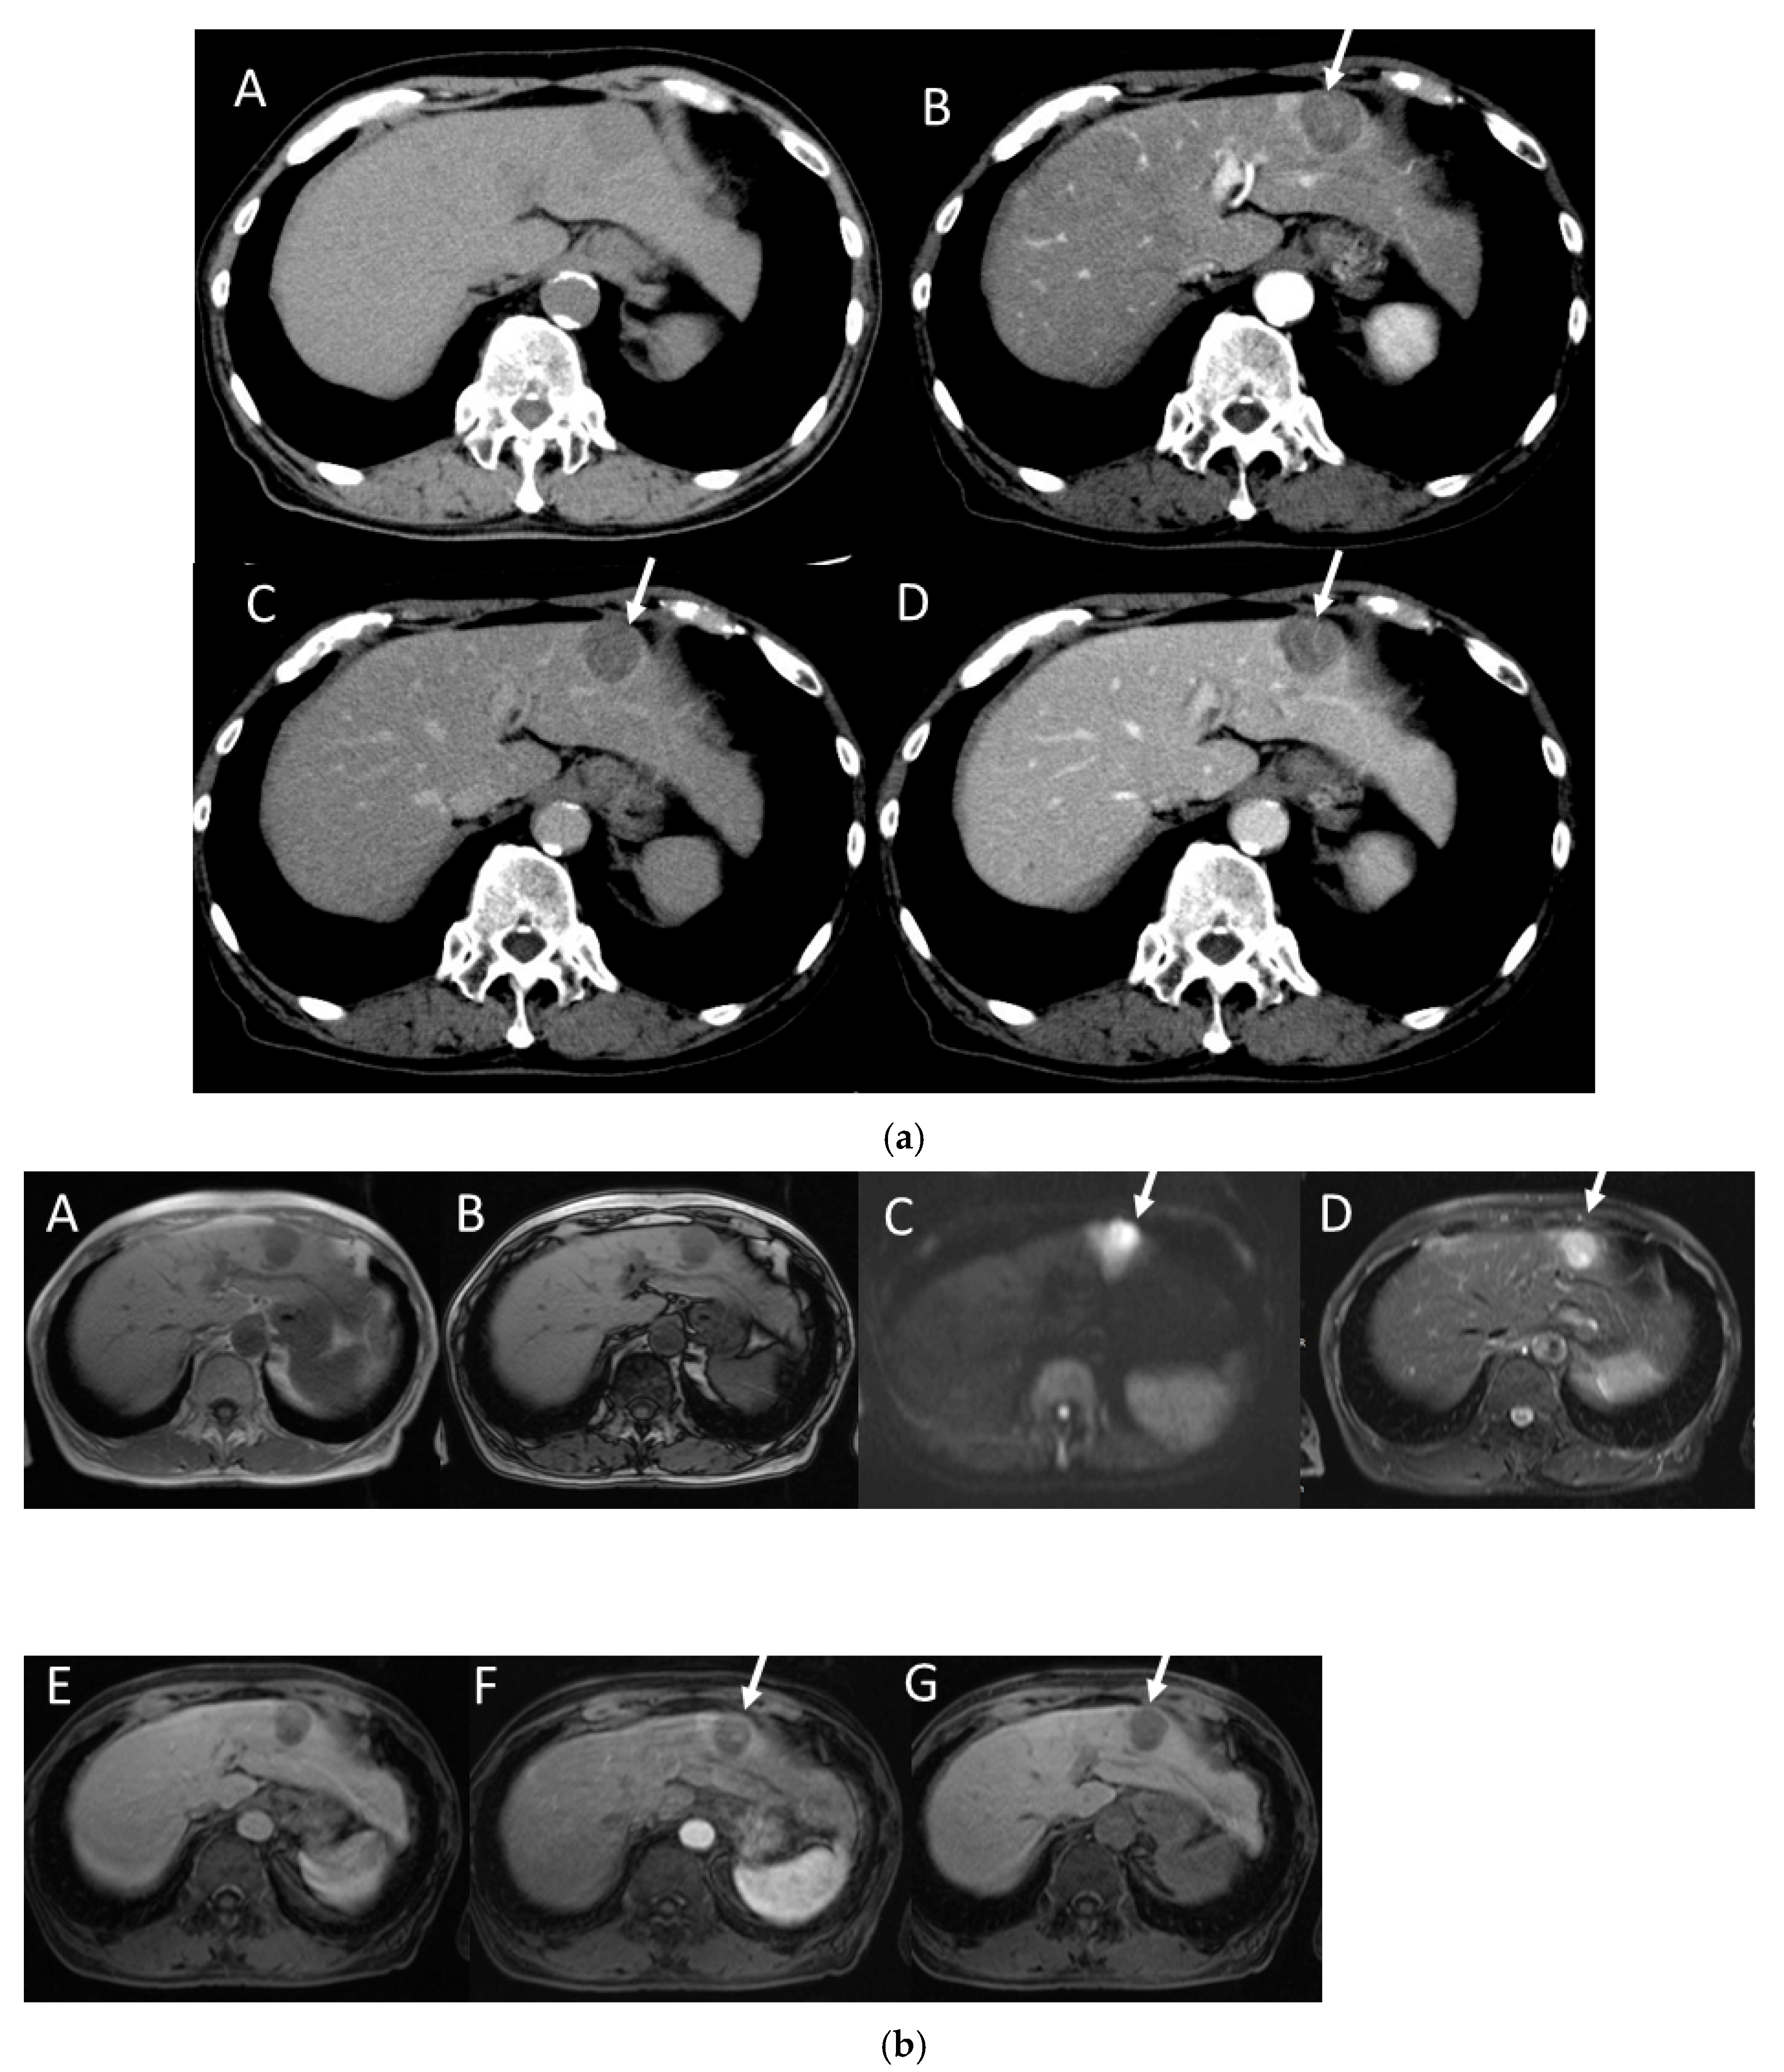

4.2. Early Hepatocellular Carcinoma (Early-HCC)

4.3. Well-Differentiated Hepatocellular Carcinoma (Well-HCC)